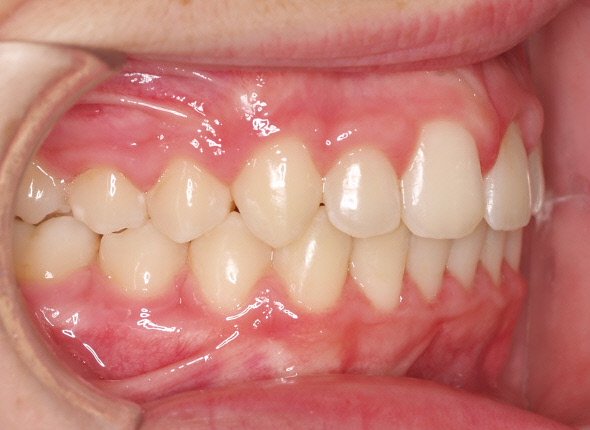

- Realizar un tratamiento ortodóncico para mover los dientes y cerrar el diastema.

Si su frenillo labial es demasiado grande, puede que le remitan a un especialista para someterse a un procedimiento quirúrgico llamado frenectomía. Este procedimiento consiste en cortar el frenillo y volverlo a colocar para permitir que tenga más flexibilidad. Cuando la frenectomía se realiza en un niño, el espacio puede llegar a cerrarse por sí solo. Si se trata de un adolescente o un adulto, puede que sea necesario cerrarlo con ortodoncia. Es esencial acudir al dentista para saber cuál de estas opciones es la adecuada en su caso.